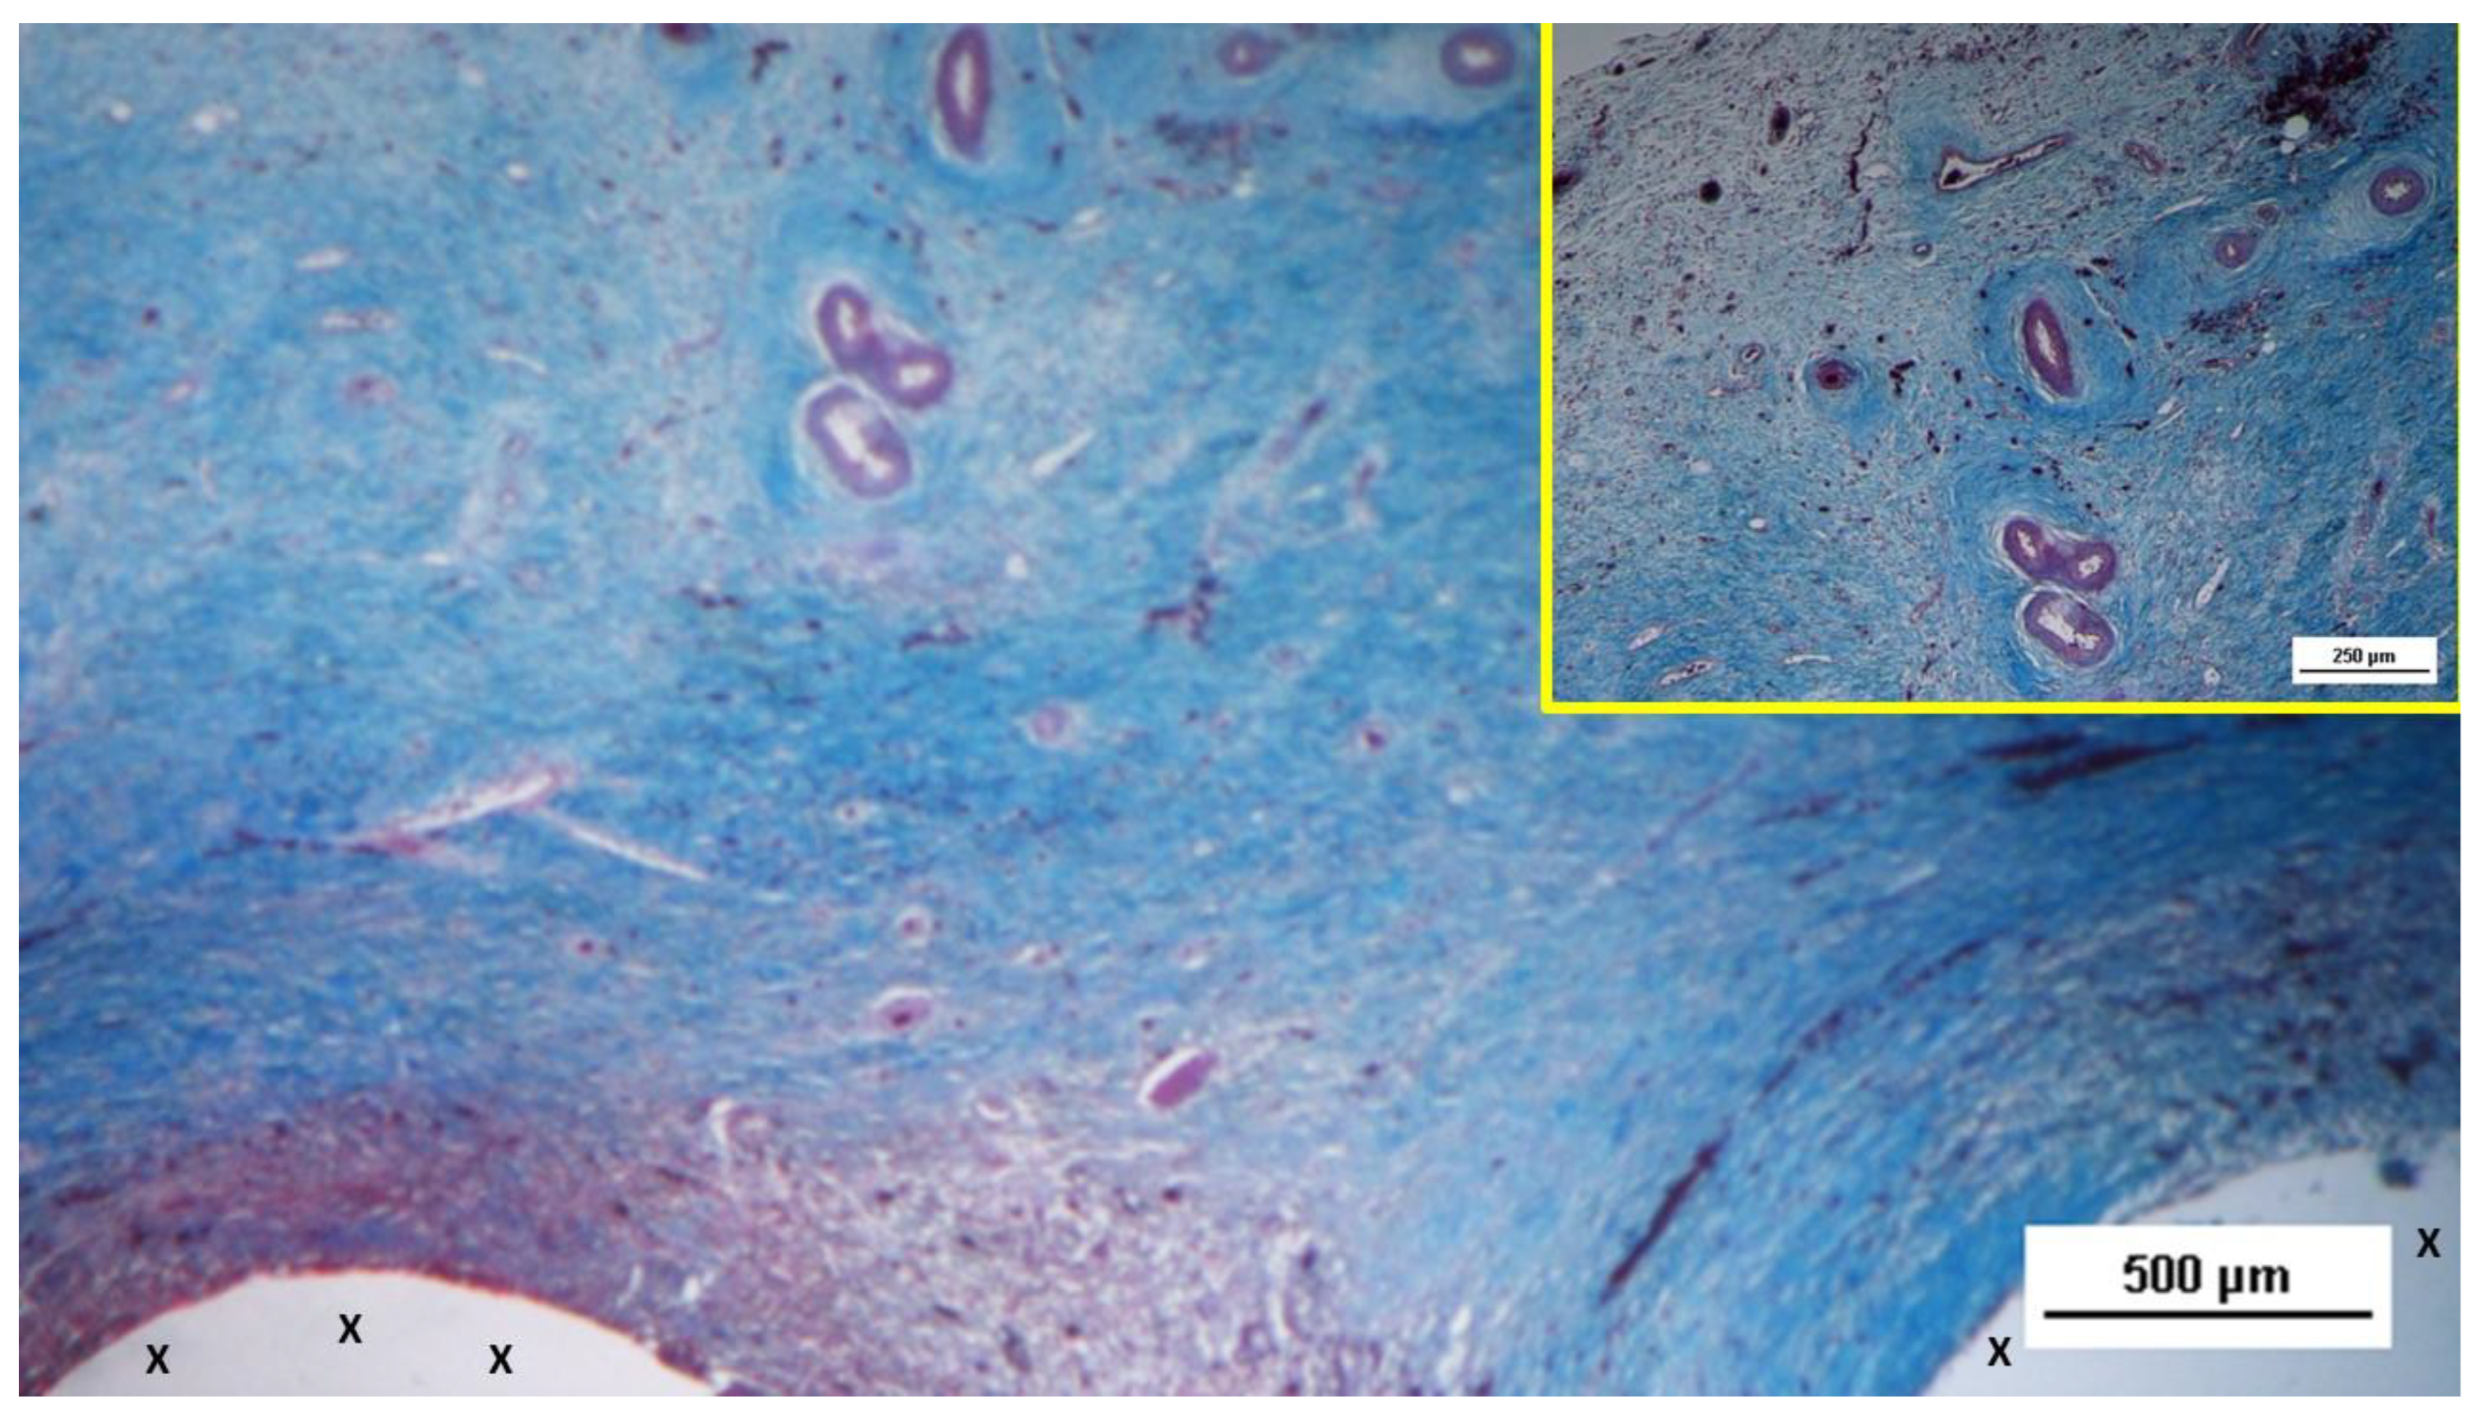

Figure 12.

Biopsy specimen excised from the 3D scaffold of the S&S device 6 months post-surgery: microphotograph showing three clusters of fully developed muscle bundles (stained in red) interspersed between two areas of adipocytes (Y) and close to a large arterial structure (yellow circle). The blue-stained tissue adjacent to the device fabric corresponds to well-perfused connective tissue. AM 25X.

In the long-term period, 5 to 8 months post-surgery, the muscular presence within the structure of the S&S device further improved, assuming the outline of mature muscular elements grouped in the characteristic bundles typical of normal muscle structure. These muscular components were disseminated within a network of interlaced connective tissue ordered along lines of force, and accompanied by numerous mature arteries and veins (

Figure 11,

Figure 12,

Figure 13 and

Figure 14).

Highly magnified images also highlighted the typical spindle-formed shape of the myocytes, with striated elements, hyperchromatic small nuclei and eosinophilic cytoplasm. This structure closely resembles that of normal human muscle bundles. [

25]